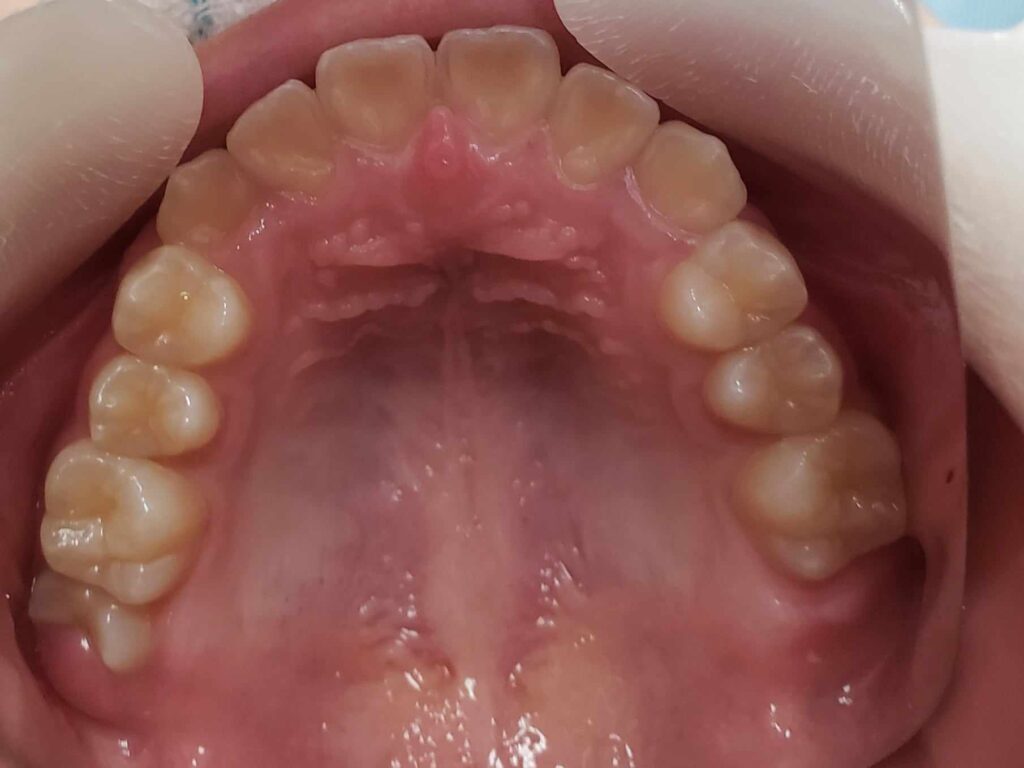

治療後

13歳頃、永久歯列になったところで、1期治療終了。虫歯のコントロール、歯磨き指導も十分に行ったため、虫歯や歯肉炎の発生もなく理想的な状態で完了できたと思います。あとは、高校1~2年生くらいに下顎の埋伏親知らずを抜歯して、通えれば20歳くらいまで半年メンテナンスが良いかもしれません。本当に口腔内の良好維持を考えている歯科医は、矯正で一時的に治った状態に満足しません。後戻りも考慮して、適齢期の親知らずの抜歯を行ったり、習癖の改善に取り組むでしょう。さらに患者さんが通院可能であれば、予後も追い続ける傾向があるでしょう。